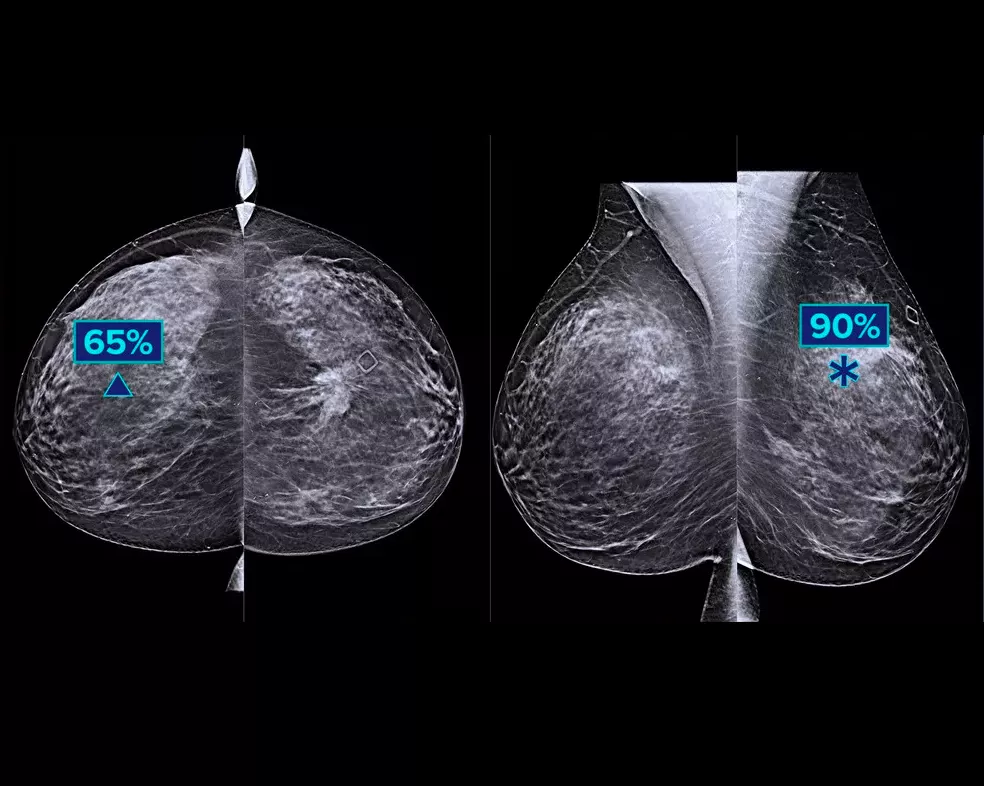

Forsøg viser en forbedring på +9 % i observeret læserfølsomhed for kræfttilfælde.1.2 Fungerer på standard- og højopløsnings-tomosyntesebilleder, overlapning på 3DQuorum SmartSlices og syntetiserede 2D-billeder.

Algoritmen ser efter 3 hovedgrupper af mistænkelige læsioner: forkalkninger, masser, densiteter og forvrængninger og enhver kombination af disse læsioner. Output kan variere på forskellige læsearbejdsstationer.

Hologic gennemførte et MRMC-forsøg (multi-reader, multi-case) for at verificere ydeevnen under brug af Genius AI-påvisningsalgoritmen.3